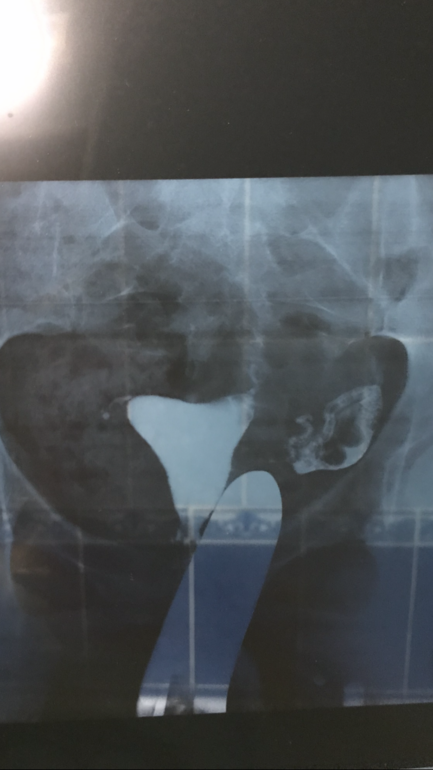

Гсг маточных труб. Пережила

ГСГ,ЭХО,МСГДевчонки посмотрите пожалуйста, может кто понимает в этом что то🤷🏼♀️Врач толком ничего не сказала

Жидкость вышла в брюшную полость но не так как хотелось бы( слова врача) что нужно лечение и что самой забеременеть без лечения никак🤷🏼♀️😞неужели все так плохо?(((((

Если что У МЕНЯ ТОЛЬКО ОДНА ТРУБА!

Труба извилистая, но проходима. А значит вполне можно Заб.

Кусочек этот смущает толи согнут толи перекручен